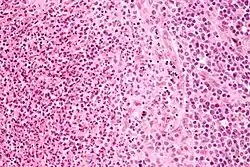

La biopsie ganglionnaire permet, outre la recherche de la bactérie ou de son ADN, de faire une analyse anatomopathologique de ce dernier[14].